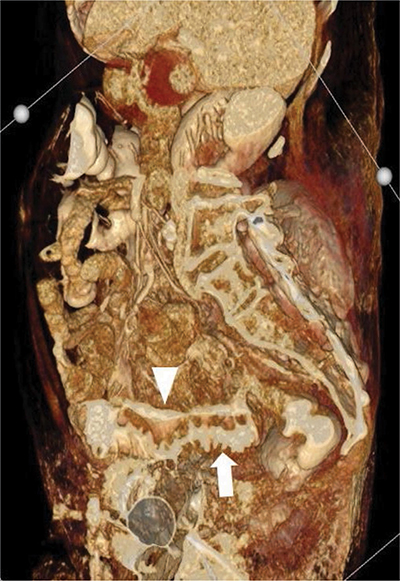

Figure 2

Volume-rendered three-dimensional reconstruction of the abdominal CT. The intramural longitudinal fistula is shown (arrowhead) to run parallel with the intraluminal contrast of the sigmoid (arrow).